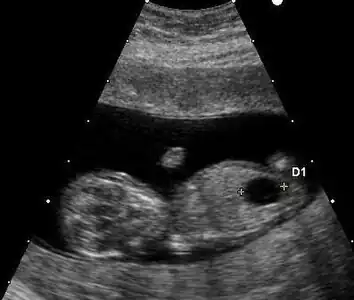

Ultrasound

Prenatal ultrasound can be used to screen for Down syndrome. Findings that indicate increased chances when seen at 14 to 24 weeks of gestation include a small or no nasal bone, large ventricles, nuchal fold thickness, and an abnormal right subclavian artery, among others.[102] The presence or absence of many markers is more accurate.[102] Increased fetal nuchal translucency (NT) indicates an increased possibility of Down syndrome picking up 75–80% of cases and being falsely positive in 6%.[103]

Ultrasound of fetus with Down syndrome showing a large bladder

Enlarged NT and absent nasal bone in a fetus at 11 weeks with Down syndrome